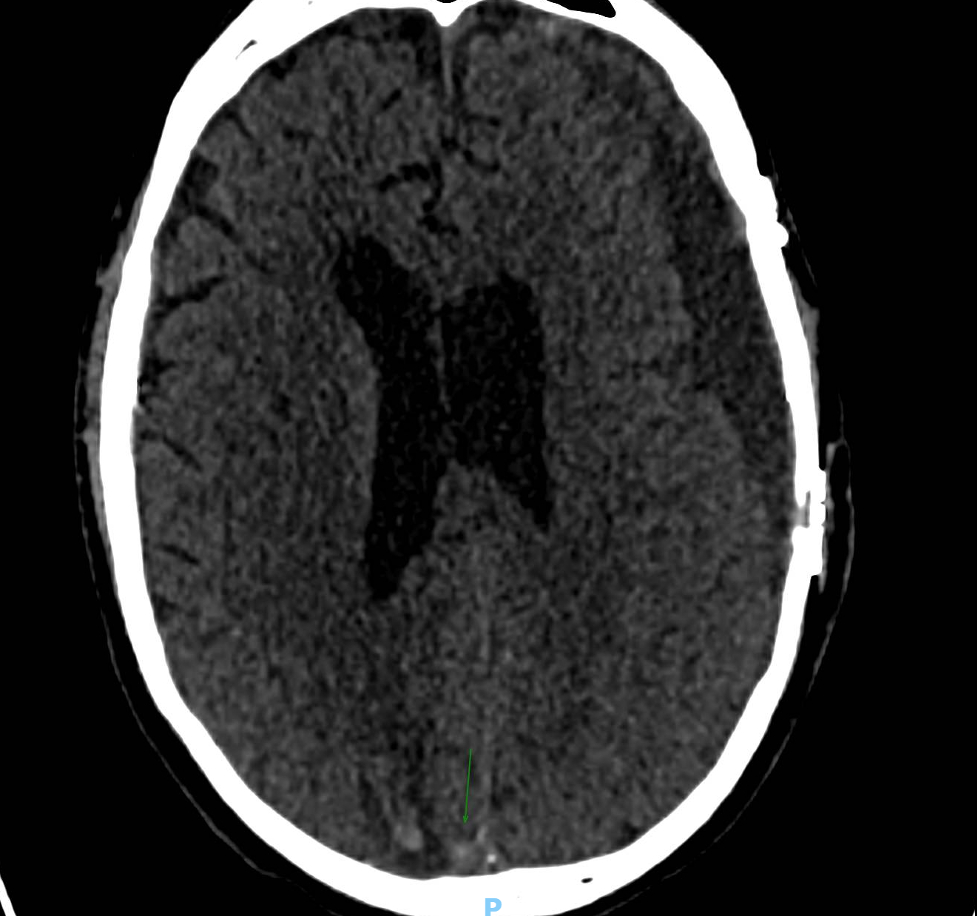

Case Summary: In less than 400 words, please summarize the case. Briefly describe the case and any particular complexities and/or complications encountered.: A 77-year-old male initially presented to our hospital after a fall with bilateral frontal contusions, traumatic subarachnoid hemorrhage, and bilateral subdural hematomas (SDH). Approximately one month later, he re-presented with altered mental status, confusion, staring spells and bilateral jerking of his lower extremities concerning for seizure activity found to have worsening bilateral chronic subdural hematomas with mass effect. He underwent hematoma evacuation with bilateral burr holes and middle meningeal artery (MMA) Onyx embolization. Three weeks later, he re-presented with generalized tonic-clonic seizures, found to have an acute intraparenchymal hemorrhage and extensive cerebral venous sinus thromboses (CVST) with embolization material seen in the transverse and superior sagittal sinuses on CT Venogram.

There are currently no specific guidelines for chronic SDH management, although MMA embolization is becoming a more widely used procedure. Our case report provides a novel description of CVST secondary to migration of the Onyx material into the dural venous sinuses after Onyx embolization for subdural hematoma that has not previously been described in the literature. This case highlights a potential complication of MMA embolization with embolization material getting into the venous system, and warrants further discussion on whether anticoagulation would be beneficial for this complication. This case also provides forum for discussion on the unique management of CVST, intraparenchymal hemorrhage, and chronic SDH.